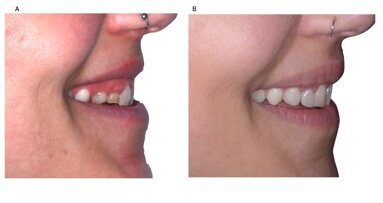

Il paziente T.M. è giunto nel mio studio a seguito della segnalazione da parte di un endodontista di Auckland. I denti 11 e 21 avevano subito un trauma importante a seguito di una caduta accidentale all’età di 7 anni. Il paziente riportava di essersi sottoposto in passato a diversi trattamenti canalari, con fallimento funzionale attribuito a infiltrazione coronale e ricontaminazione, nonché fallimento estetico associato a pigmentazione scura dovuta a ritenzione di emosiderina e penetrazione di massa batterica.

I denti 11 e 21 presentavano vecchi restauri in composito descritti come decolorati, disomogenei e inaccettabili, che causavano ansia al paziente. In aggiunta a questo quadro complesso, era presente una perforazione subgengivale nell’immediata regione medio-buccale subgengivale, che causava irregolarità gengivale con una tasca parodontale risolta di recente. L’aspetto distale del dente 21 era sottocontornato, con un conseguente guscio sublinguale o sottosquadro in questa regione, con un profilo d’emergenza insufficiente. Il paziente desiderava incisivi centrali più regolari, più lunghi ed estetici, ma vi erano limiti legati a fattori economici e alla struttura dentale residua.

Con il paziente si è valutato il posizionamento di due faccette dirette in composito con stratificazione complessa, al fine di correggere il problema estetico, con asportazione di una minima quantità di struttura dentale. I rapporti ampiezza-altezza sarebbero stati migliorati fino a portarli a un rapporto pari a 0,8 : 1,0 per le proporzioni ideali. Al paziente è stata prospettata anche l’opzione di restauri adesivi in ceramica, in quanto questi avrebbero avuto un effetto positivo sul rafforzamento coronale. Sebbene il paziente e sua madre fossero interessati a questa opzione, il desiderio del paziente di riparazione in caso di futuri incidenti e le condizioni economiche rappresentavano fattori limitanti. Il paziente ha quindi accettato il consiglio di applicare faccette dirette stratificate in composito sui denti 11 e 21.

Dopo la polimerizzazione finale, i contatti sono stati aperti mediane una lieve forza di separazione interdentale (“Mopper Pop”) e rifiniti con strisce in metallo abrasive medie e fini (GC) nonché con strisce abrasive in polimero Epitex (GC). Con una matita sono state eseguite delle marcature sulla superficie labiale per guidare la conservazione degli angoli lineari e del profilo di emergenza. La finitura dell’anatomia primaria e secondaria è stata completata con dischi abrasivi a grana grossa (Soflex, 3M ESPE) e frese diamantate fini (Mani Dia-Burs). La lucidatura è stata completata con il sistema Double Diamond two-step (Clinician’s Choice) a 5000 giri/min per un’elevata brillantezza, seguita dall’applicazione di una pasta all’ossido di alluminio (Enamelize, Cosmedent) mediante feltrino (Flexibuff, Cosmedent). Il paziente è stato dimesso in attesa della guarigione gengivale e la polimerizzazione completa del composito, in vista del successivo richiamo per la lucidatura finale.